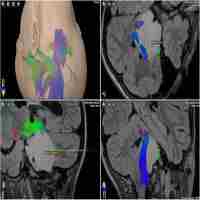

| Abstract | BACKGROUND: (blind field). METHODS: Patients with recurrent high grade gliomas were enrolled in one of two arms. Group A patients (clinical assessment group) received a single intratumoral injection of DNX-2401 into biopsy-proven recurrent glioma. Group B patients (biological endpoint group) received an initial intratumoral injection through a permanently implanted catheter (to identify the injection site) followed 14 days later by en bloc tumor resection (to obtain post-treatment specimens) and subsequent injection of DNX-2401 into the post-resection tumor bed. Dose was escalated from 1x10^7 to 3x10^10 viral particles (vp) in 8 cohorts. Patients were followed with clinical exams, MRIs, and laboratory studies. RESULTS: Histological analysis of post-treatment en bloc surgical specimens cut perpendicular to the implanted catheter proved for the first time that DNX-2401 was capable of infecting, replicating in, and killing human glioma tumor cells (Group B; N = 12). The maximum dose achieved was 3 × 10^10 vp as planned (Group A; N = 25). DNX-2401 resulted in no toxicity in each cohort. Ongoing outcome analyses show an overall median survival of 11 months. Remarkably, complete responses were seen in 3 patients (12%) (#12, #33, #37), all of whom are currently alive with no evidence of disease (3.2, 2 and 1.75 years after treatment). Serial MRIs revealed a period of increased enhancement prior to tumor regression, consistent with an inflammatory response. Histological analysis of a resected tumor from a symptomatic patient (#20) in Arm A during this period of increased MRI-enhancement identified primarily inflammatory cells (macrophages/CD8 T-cells) and only rare glioma cells. Analyses of inflammatory cytokines in serum revealed that, compared with all other patients, the 3 responders had 10-fold to 10,000-fold increases in Interleukin-12p70 (which polarizes T(h)0-cells to T(h)1-cells and promotes cell-mediated immunity). CONCLUSIONS: DNX-2401 is a new oncolytic virus with a favorable toxicity profile that is capable of replicating in and killing human glioma cells. Efficacy in this early stage trial was impressive with a 12% complete response-rate that has proven to be durable. Molecular studies suggest that viral-induced, anti-tumor cytotoxic immunity (in situ vaccine) may play a role in the anti-glioma effect of DNX-2401. SECONDARY CATEGORY: Immunobiology & Immunotherapy. |